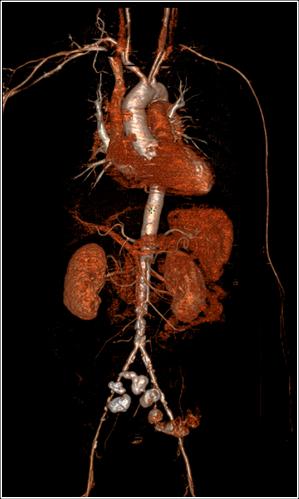

西安盈谷科技accuradpro 3d高级图像处理系统的增强功能,体数据下的组织分割功能,用于感兴趣区域血管自动/半自动交互提取。

多斜位mpr是完全基于容积数据处理(volume data processing,简称vdp)的处理方式,医生可以对容积扫描的数据在完整的体数据下,按照任意厚度、任意角度和任意曲面下,做平均值、最大/最小密度、容积重建、积分图像处理。